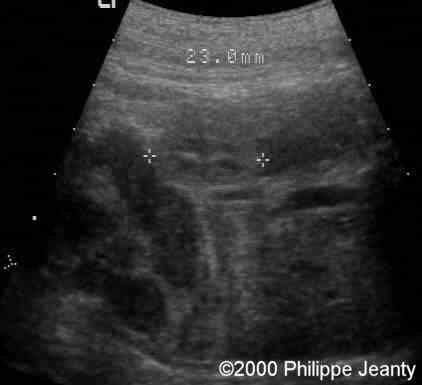

One kidney length was 23 mm (5th percentile: 36mm, mean: 41, 95th percentile: 46mm)

case0020-6a

The other is 29 mm. So both kidneys are just a little above half the normal size ! Surprisingly this was not recognized by many.

case0020-6b